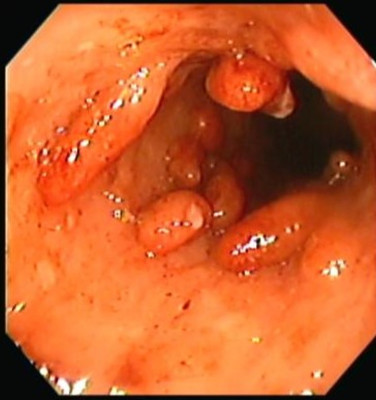

Pólipos de colon

Envíado por Dr. Carlos Ernesto Arévalo